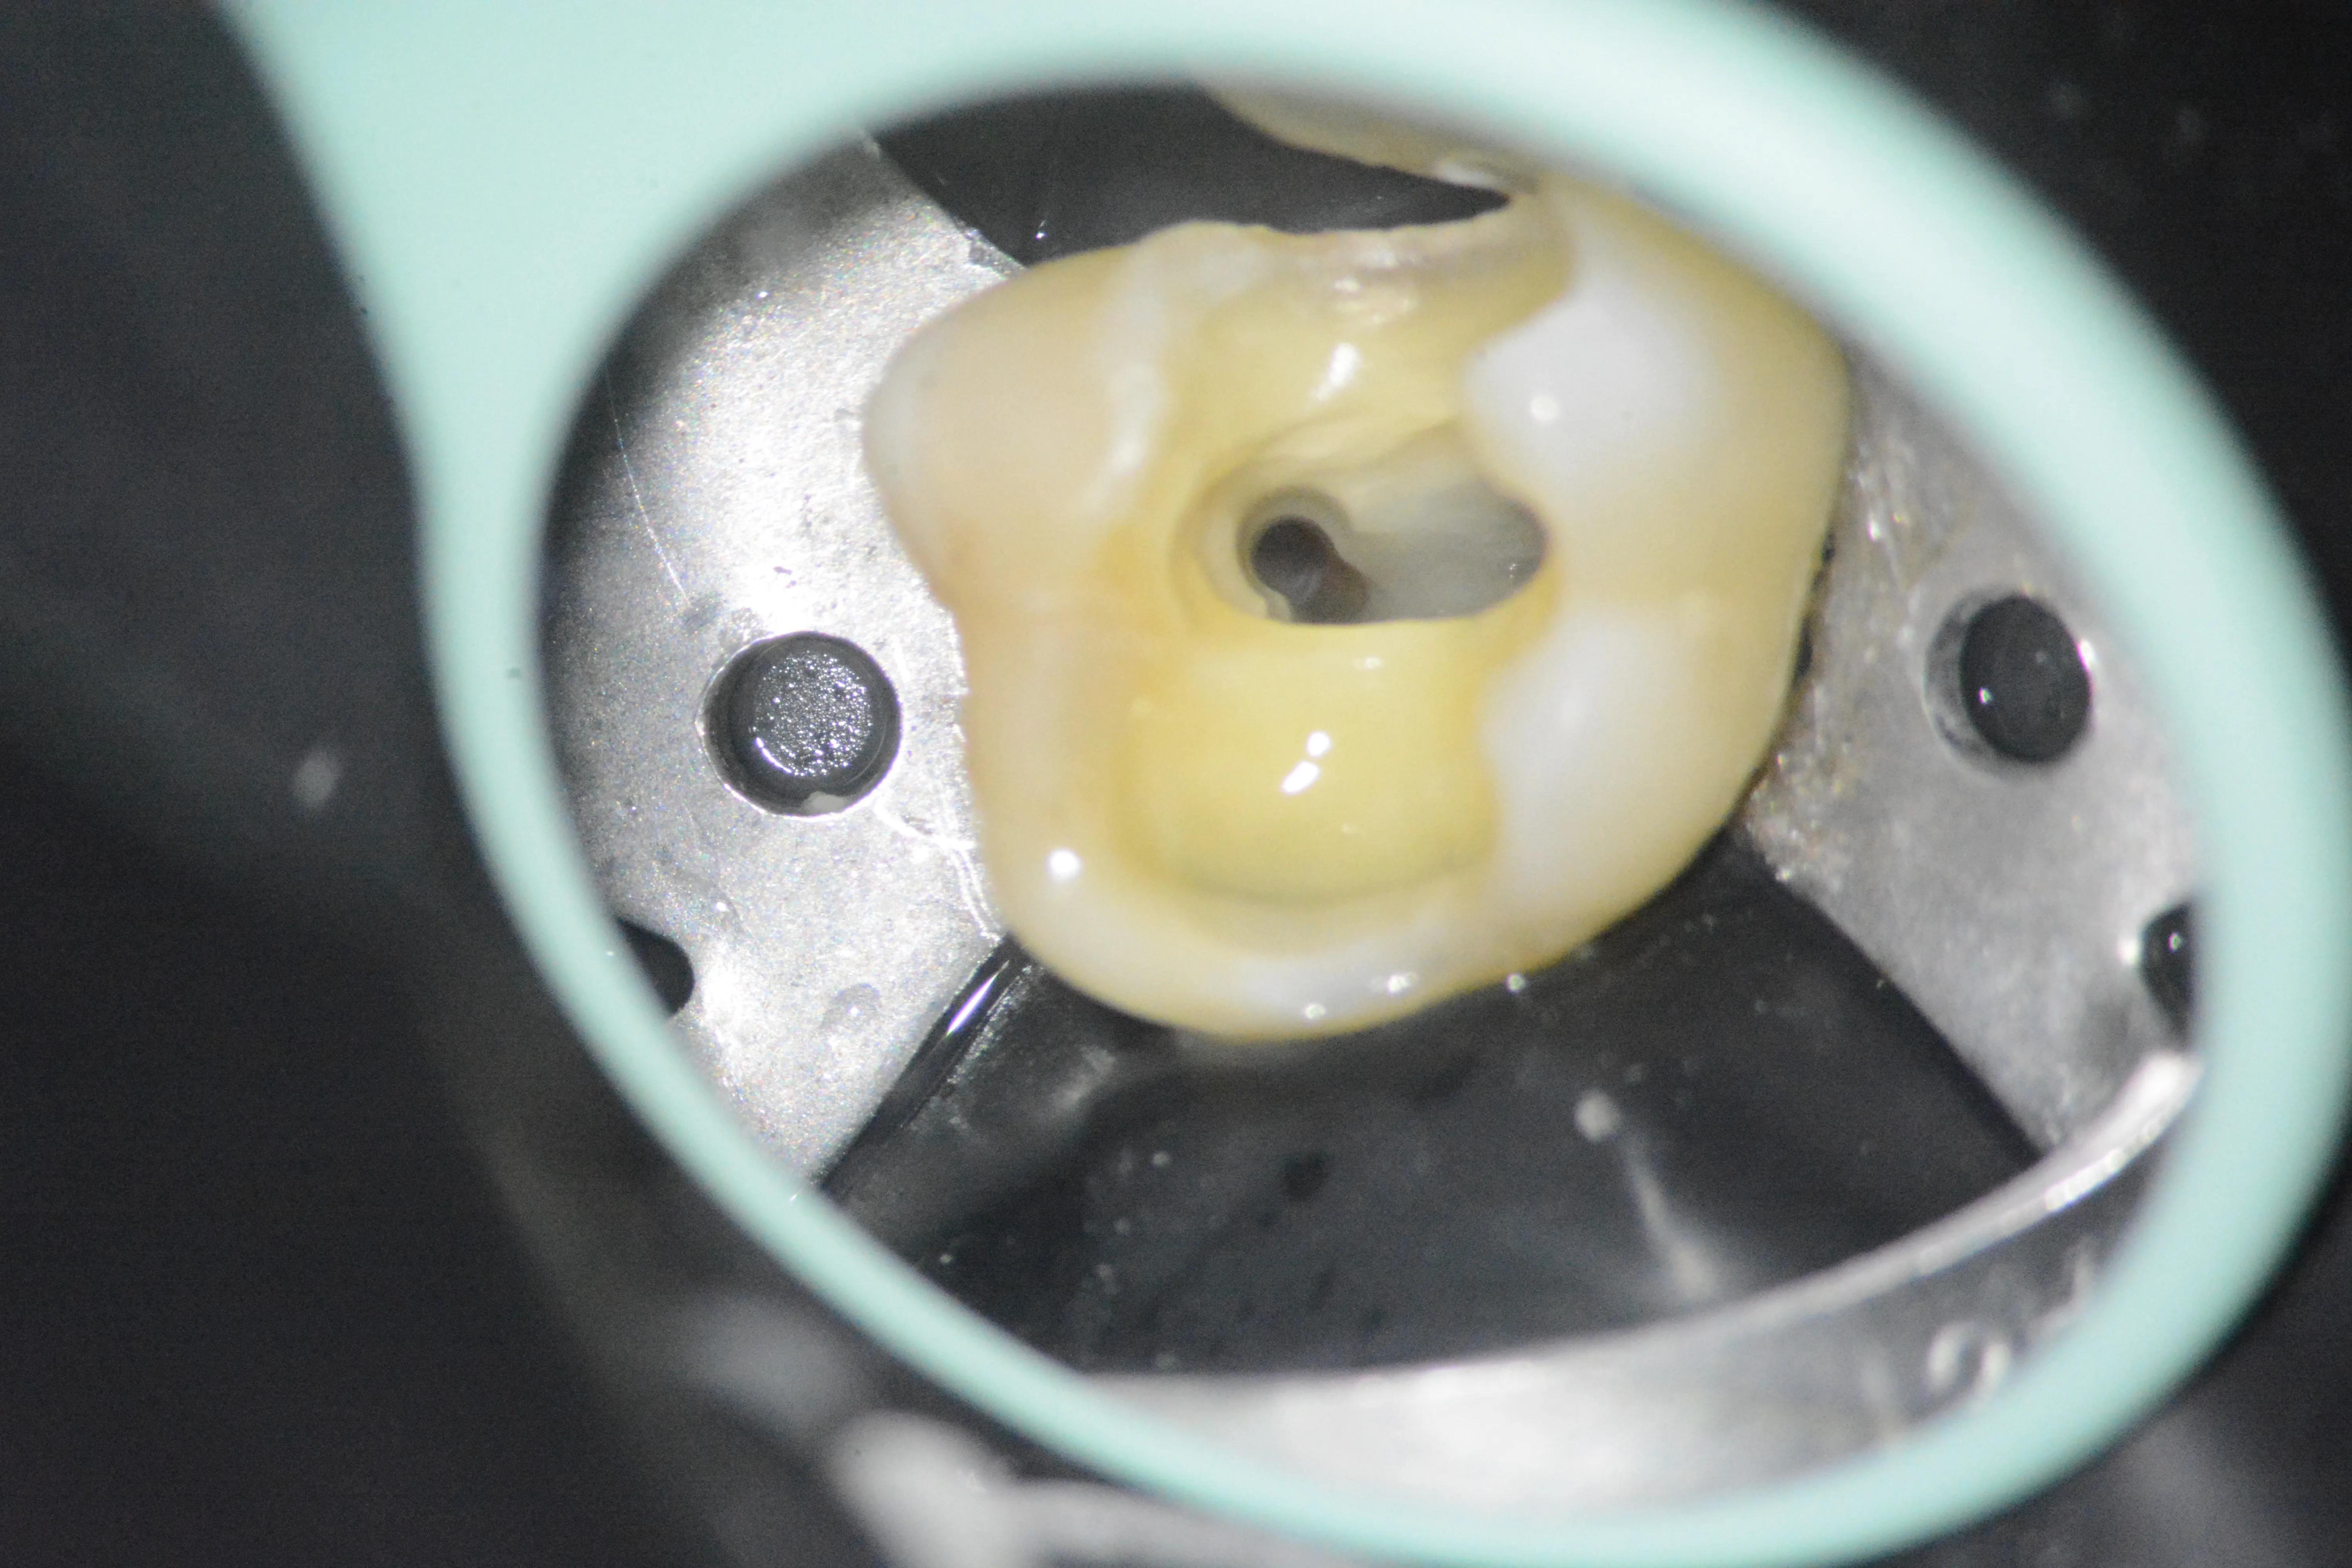

5 – Aspectul sistemului mezial după finalizarea tratamentului mecanico-antiseptic